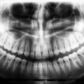

Gingivitis qué es, síntomas y tratamiento